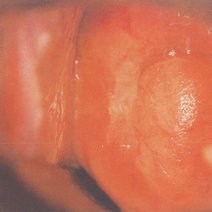

- 滴虫性阴道炎滴虫性阴道炎滴虫性阴道炎是经细菌传播引起的。引起滴虫性阴道炎的途径是经性交传播、经公共浴池、浴盆、浴中、游泳池、厕所、衣物、器械及敷料等途径。滴虫性阴道炎的症状是外阴和阴道瘙痒、有灼热感甚至疼痛,同时白带增多,呈黄白色脓性、泡沫

滴虫性阴道炎是由阴道毛滴虫引起的一种阴道炎。患者症状主要是稀薄的泡沫状白带增多及外阴瘙痒,可伴有烧灼感、疼痛和性交痛。治疗方案有全身用药和局部用药。滴虫性阴道炎患者的丈夫或...